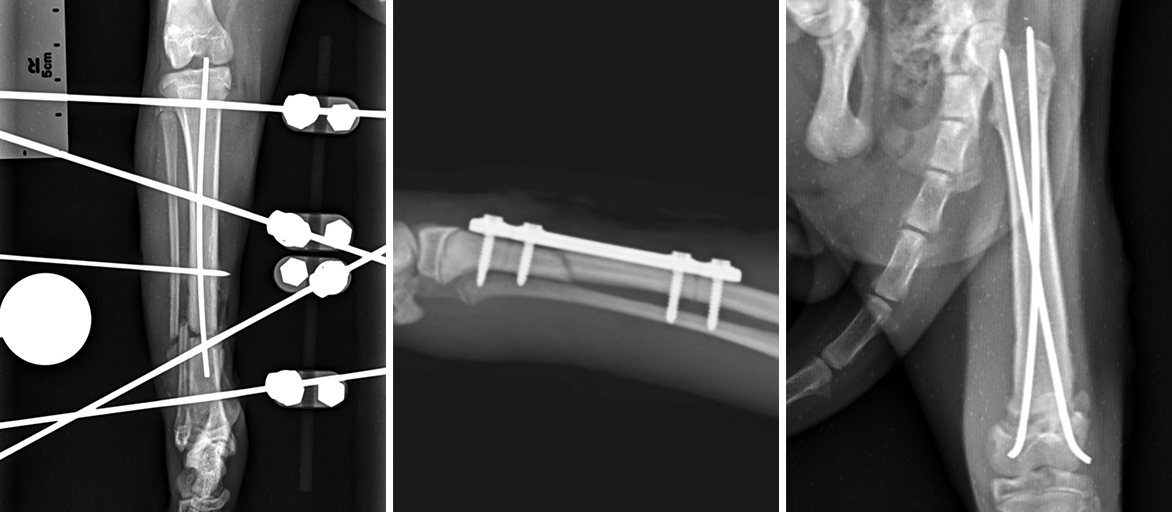

External fixation device (pins and bar clamp) may be surgically threaded into the bone and exit from the skin

Internal Implants with plates, screws, wires, and/or pins may be surgically implanted inside the bone or on its surface